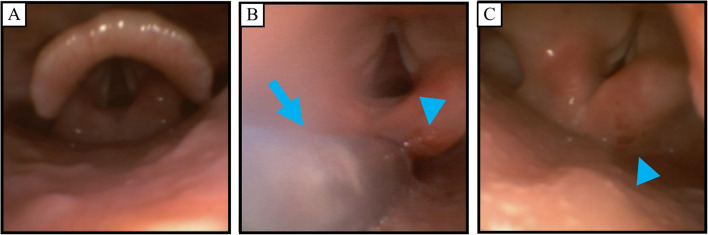

Case presentation: A 35-year-old woman with myasthenia gravis was scheduled for laparoscopic ileocolic resection. FEES was performed before anesthesia, after extubation, and on postoperative day 1. General anesthesia was performed with endotracheal intubation, and extubation was performed uneventfully. Post-extubation FEES revealed salivary pooling, decreased glottal closure reflex, and redness of right arytenoid, likely caused by the endotracheal intubation and nasogastric tube. However, FEES performed on postoperative day 1 showed improvement of these findings.